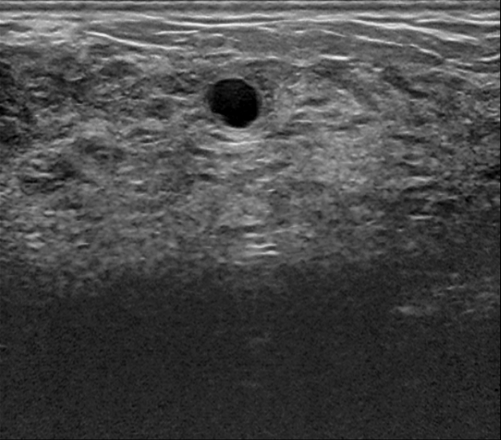

To validate the zero-shot and weakly supervised segmentation results, as well as different design components of the MedCLIP-SAM framework, we used three public datasets (three different modalities) with segmentation ground truths (segmentation of breast tumor, brain tumor, and lung), which were split for training, validation, and testing. These datasets with their divisions include:

• Breast Tumor Ultrasound: Breast Ultrasound Images dataset (BUSI) [1] with 600 benign and malignant tumors images for training only; 65 and 98 images from the UDIAT[5] dataset for validation and testing, respectively.

In Table 3, we present segmentation accuracy for our proposed method in zero-shot and weakly supervised settings, with fully supervised segmentation as a reference. Note that for zero-shot results, we include a comparison between initial labels generated by gScoreCAM-based saliency maps (“Saliency Maps”) and pseudo-masks from SAM (“Saliency Maps + SAM”). Combining BiomedCLIP and SAM demonstrates clear advantages, notably improving segmentation quality for all metrics (p<0.05𝑝0.05p<0.05). Comparing zero-shot results to weakly supervised segmentation, we observe general improvements for X-ray-based lung segmentation. However, the impact on tumor segmentation in breast ultrasound and brain MRI remains unclear, with an AUC boost of similar-to\sim2% only for breast ultrasound. While fully supervised DL models currently provide state-of-the-art accuracy for medical image segmentation, our MedCLIP-SAM zero-shot segmentation outperformed ResUNet-based full supervision for breast ultrasound and brain MRI segmentation. Lung X-ray segmentation, however, showed superior accuracy with the fully supervised method across all metrics. Finally, to provide a qualitative assessment, exemplary segmentation results for zero-shot and weakly supervised settings are shown in Fig. 2 against the original image and ground truths (GTs) across all segmentation tasks.